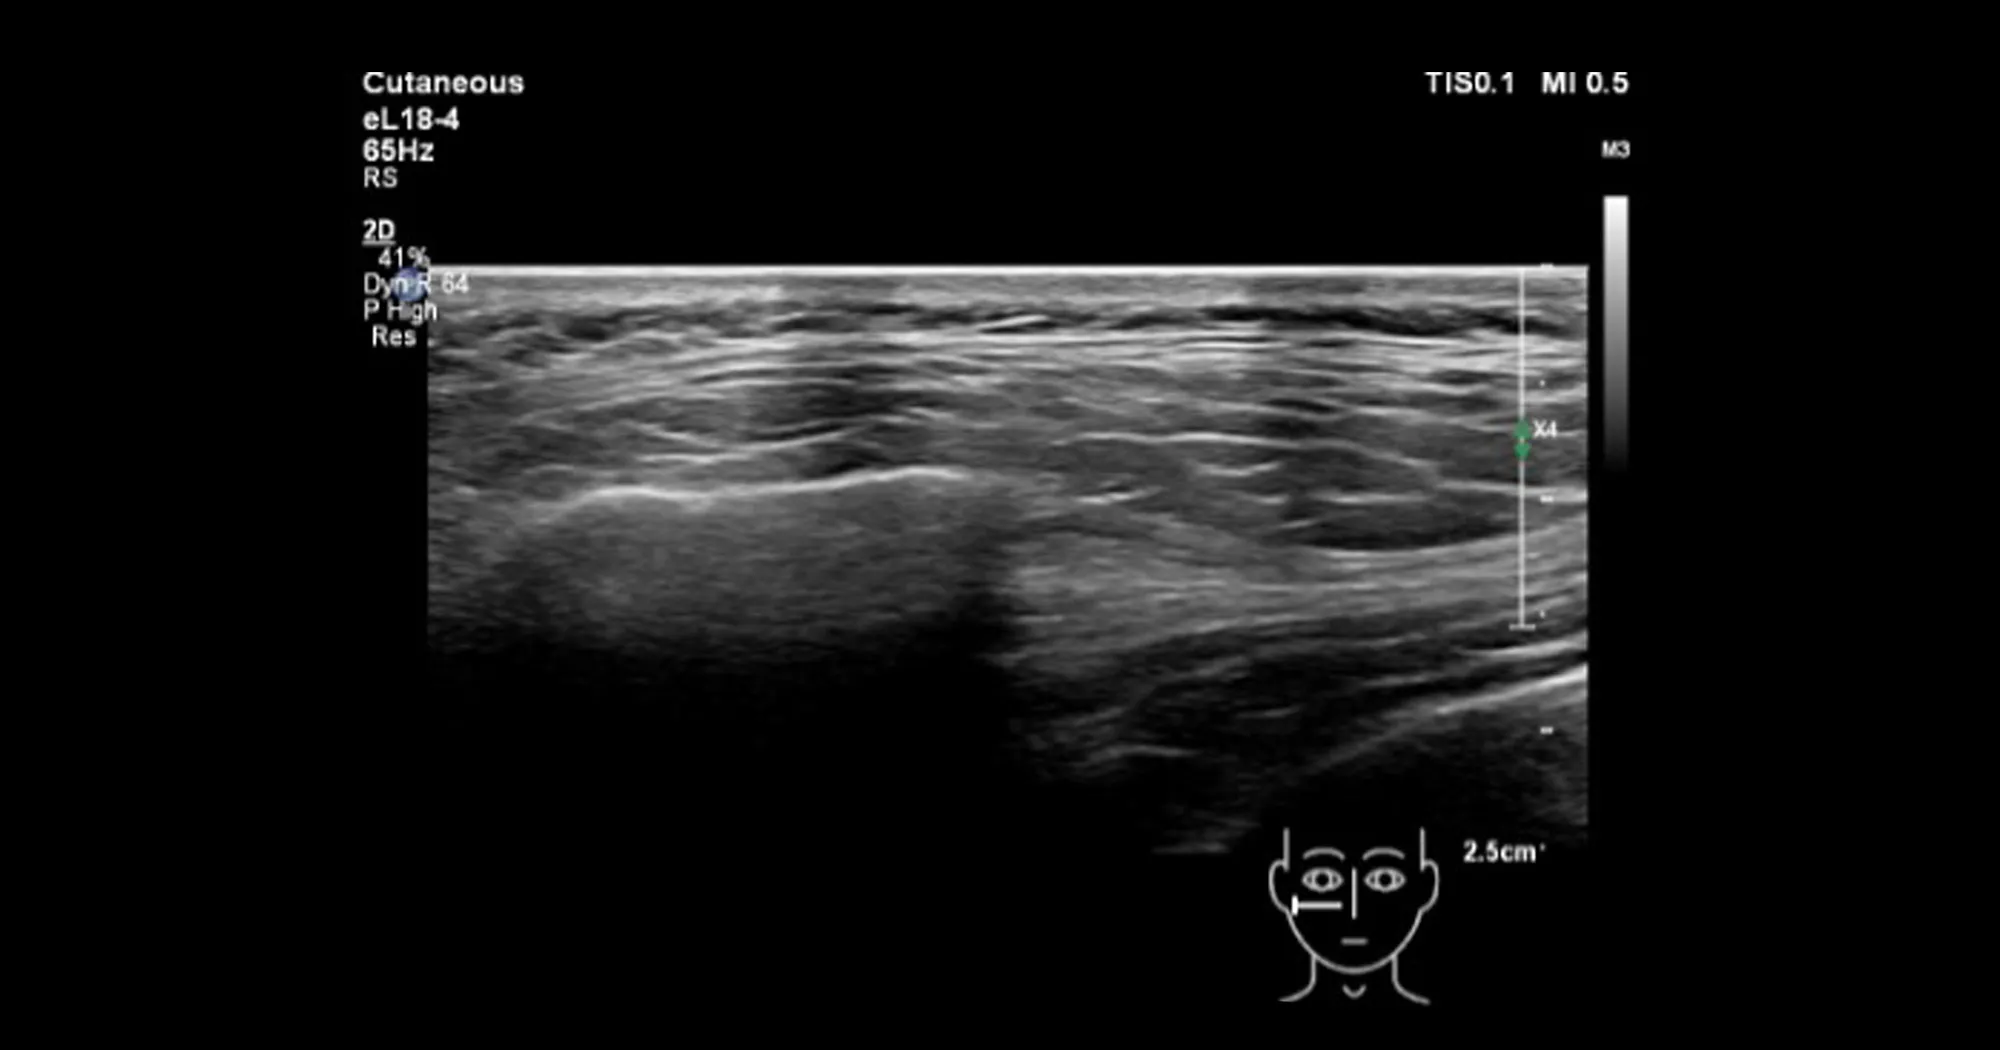

When comparing Figure 1 to a real ultrasound image that was taken from the cheeks (of an aesthetic patient) big differences can be observed. The most striking difference is that no clear separation exists between the fascial layers as shown in Figure 1 and that the superficial and the deep fatty layers are not homogeneous within themselves but instead highly structured and continuous with each other.

Figure 2: Ultrasound image of the cheeks in horizontal orientation. With permission from Dr. Leonie Schelke.

This ultrasound image does not correspond to the current concept of the layered arrangement of the face (as shown in Figure 1), and it seems that theory is far away from reality in this case. To make things even worse, I conducted a cryosection of the cheek region back in 2015 and have found upon review of these old datasets interesting similarities between the ultrasound image (of a living patient) and of a human body donor as shown in Figure 3 below.

Both the cryosection (Figure 3) and the real-time ultrasound of the cheek (Figure 2) show that no clear separation exists between the various fatty layers but instead they all seem connected with each other. In addition, it seems that there are multiple fascial layers present and not only a superficial and a deep fatty layer. Distinct and detailed fat compartments with strong compartmental boundaries seem to not be present but instead a highly structured and organized 3-dimensional connective tissue network that spans from the deep layers to the dermal undersurface and envelopes the various fat lobules.